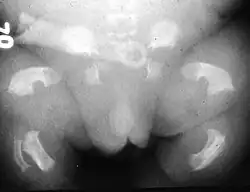

| Radiogram of a baby born with thanatophoric dwarfism | |

Infants with this condition have disproportionately short arms and legs with extra folds of skin. Other signs of the disorder include a narrow chest, small ribs, underdeveloped lungs, and an enlarged head with a large forehead and prominent, wide-spaced eyes. Thanatophoric dysplasia is a lethal skeletal dysplasia divided into two subtypes. Type I is characterized by extreme rhizomelia, bowed long bones, narrow thorax, a relatively large head, normal trunk length and absent cloverleaf skull. The spine shows platyspondyly, the cranium has a short base, and, frequently, the foramen magnum is decreased in size. The forehead is prominent, and hypertelorism and a saddle nose may be present. Hands and feet are normal, but fingers are short. Type II is characterized by short, straight long bones and cloverleaf skull.[1] It presents with typical telephone-handle shaped long bones and H-shaped vertebrae.

Infants with type 1 thanatophoric dysplasia also have curved thigh bones, flattened bones of the spine (platyspondyly) and shortened thoracic ribs. Note: Prenatal ultra-sound images of the ribs sometimes appear asymmetrical when in fact they are not. In certain cases, this has caused a misdiagnosis of osteogenesis imperfecta (OI) type II.